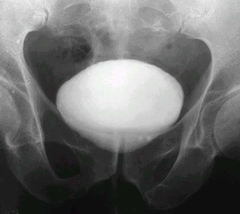

男性膀胱結石夏季為何多呢?最近幾年,膀胱結石患者數量是直線上升的。大部分患者是男性,這是為什么呢?特別是在夏季的時候,真是什么原因呢?齊齊哈爾?現代醫院的結石專家將為您解開疑惑。

齊齊哈爾?現代醫院的專家表示:夏季是尿路結石發病的旺季。中醫講“如水煮鹽,火大水少 ,漸成石”。在熱帶地區生活的人易患尿路結石,我國南方尿路結石的發病率較高,這說明 尿路結石除了病理性因素外,還與高溫有關。據統計,夏季結石發病率為平時3倍。另外, 臨床實踐也證明,每逢炎熱季節氣溫驟升時,尿結石病人腎絞痛的發生率比冬季明顯增加。

夏季尿結石高發,主要是因為天氣炎熱導致輸尿管處于擴張狀態,當腎盂內尿液減少時 ,原來浮游于尿液中的結石下落到輸尿管狹窄部位,造成急性梗阻而引起疼痛發作。此外, 在丟失水分后,血液中溶質增加,容易析出新的結石。因此夏季一定要根據自己的情況,適 當多飲水。